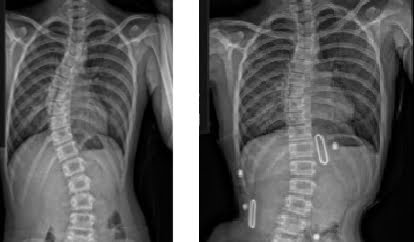

قبل و بعد

قبل و بعد

حتى أولئك الذين يعانون من اعوجاج العمود الفقري الشديد، حيث تزيد زاوية كوب عن 40 درجة، فقد استجابوا جيدًا لطريقه العلاج التي تعتمد على أحزمه الجنف تشينو-جينسينجن وبرنامج العلاج الطبيعي الذي يتبع مبادئ العلاج الطبيعي في شروث.